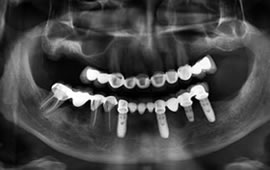

Being able to fabricate an implant retained upper or lower bridge was only a dream a few years back regaining taste and ability to chew without fear are major achievements not to mention being able to maintain teeth as if they were your own. Difficult to phathom but true these days. If you are tired of denture adhesives and wish to explore your possibilities, please do not hesitate to contact us or send your x-rays via email.

See photos of a complete dental implant case